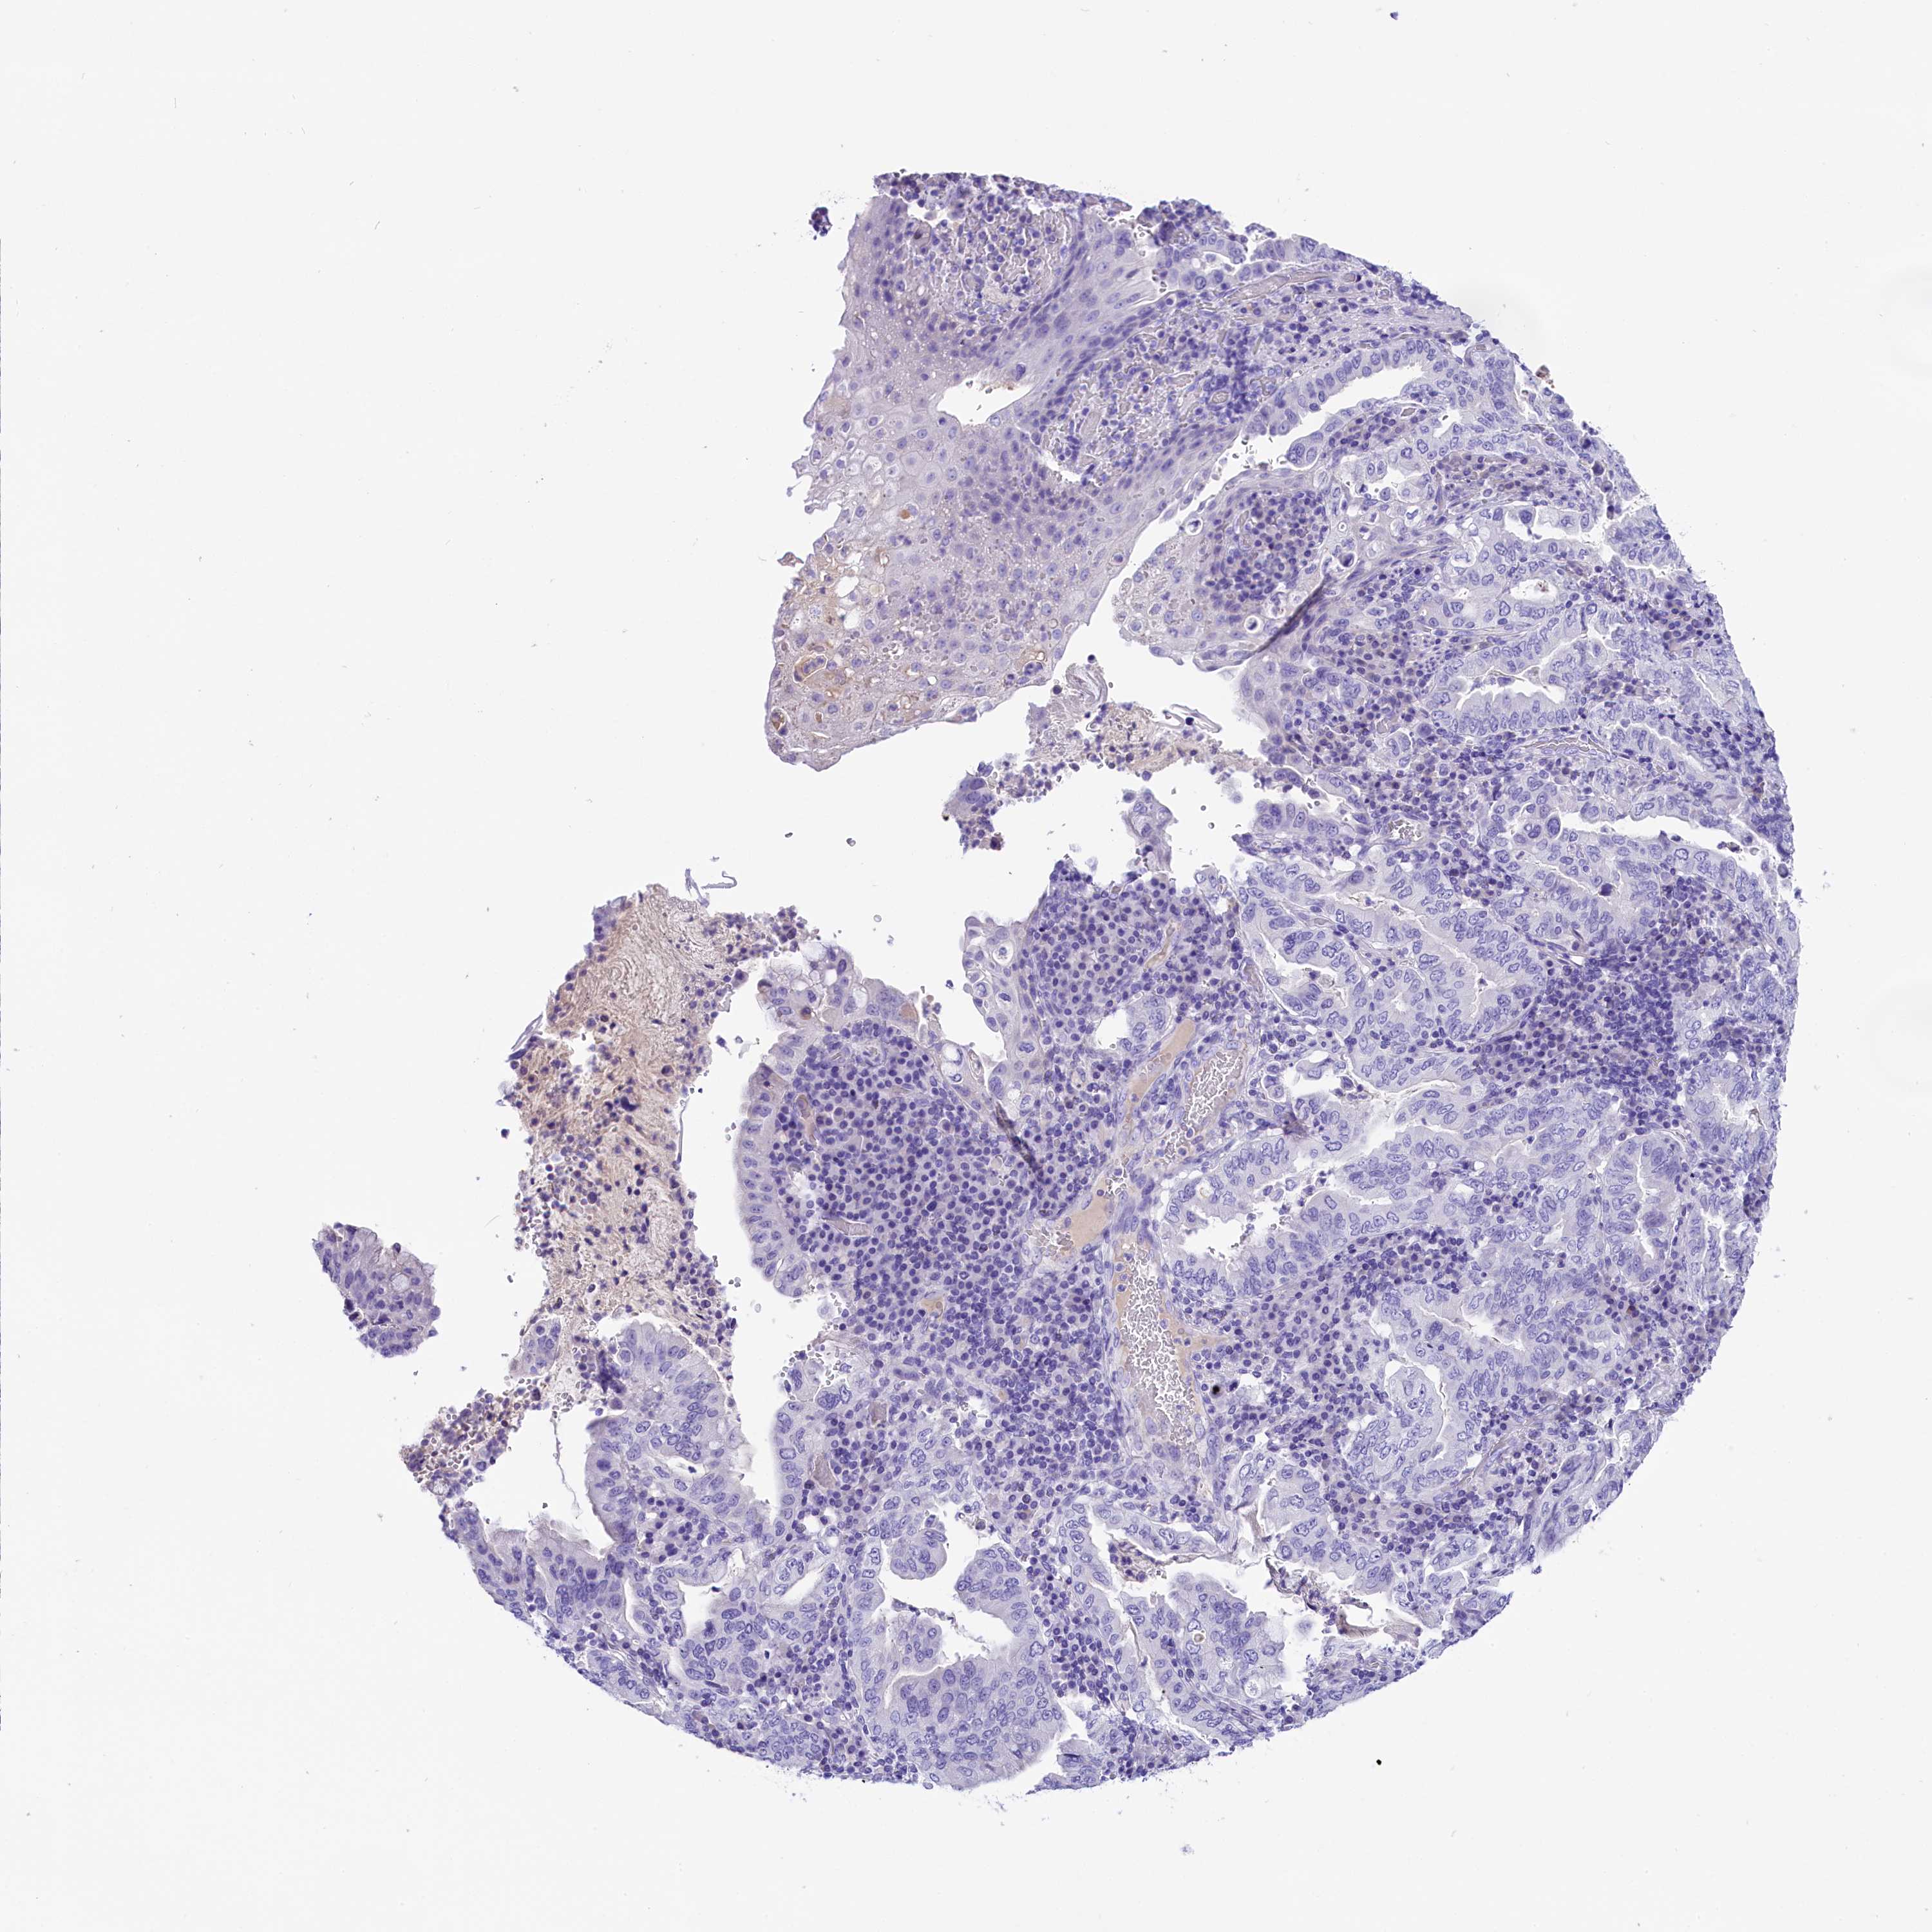

STOMACH CANCER - Protein expressioni

A mouse-over function shows sample information and annotation data. Click on an image to view it in a full screen mode. Samples can be filtered based on level of antibody staining by selecting one or several of the following categories: high, medium, low and not detected. The assay and annotation is described here.

Note that samples used for immunohistochemistry by the Human Protein Atlas do not correspond to samples in the TCGA dataset.

Antibody stainingi

Antibody staining in the annotated cell types in the current human tissue is reported as not detected, low, medium, or high, based on conventional immunohistochemistry profiling in selected tissues. This score is based on the combination of the staining intensity and fraction of stained cells.

Each image is clickable and will lead to virtual microscopy that enables deeper exploration of all samples and also displays staining intensity scores, fraction scores and subcellular localization as well as patient and tissue information for each sample.

Antibody HPA039208

Antibody HPA040439

Staining

High

Medium

Low

Not detected

Intensity

Strong

Moderate

Weak

Negative

Quantity

>75%

75%-25%

<25%

None

Location

Nuclear

Cytoplasmic/membranous

Cytoplasmic/membranous,nuclear

Adenocarcinoma, NOS

Adenocarcinoma, High grade